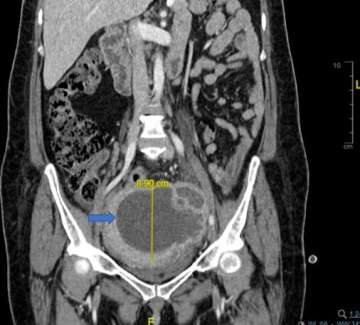

Disguised as Ovarian Tumor: A Rare Case of Uterine Abscess due to Hypervirulent Klebsiella pneumoniae Infection

•A seemingly ovarian tumor turned out to be an infection (uterine abscess) caused by an emerging pathogen named hypervirulent Klebsiella pneumonia (hvKp), discovered by the clinical genotyping capability of the UCLA MMPG lab, which helped preserve the patient’s right ovary, and contributed to a successful treatment. This case highlights the importance of a multidisciplinary effort for the effective diagnosis and management of hvKp infections, which is on the rise in the SoCal community.